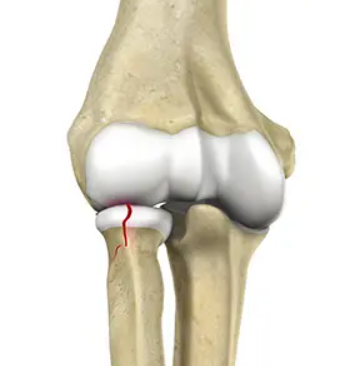

요골머리 골절(요골두 골절)은 팔꿈치 부위 요골 상부, 특히 요골머리(요골두)에 발생하는 골절입니다. 주로 팔을 펴고 넘어지면서 손으로 땅을 짚을 때 생기며, 팔꿈치에서 가장 흔한 골절 중 하나입니다. 낙상이나 스포츠 활동 중에 많이 발생합니다.

여러 각도에서 촬영한 X-레이 검사가 기본이며, 요골두 골절은 골절선이 잘 보이지 않는 경우도 있어 진단이 어려울 수 있습니다.

♼ 분류 (Mason 분류)

1형: 전위가 없거나 2mm 미만의 골절(그림A)

2형: 관절면 30% 이상 포함, 2mm 이상의 전위 골절(그림B)

3형: 분쇄골절(그림C)

4형: 탈구가 동반된 골절(그림D)